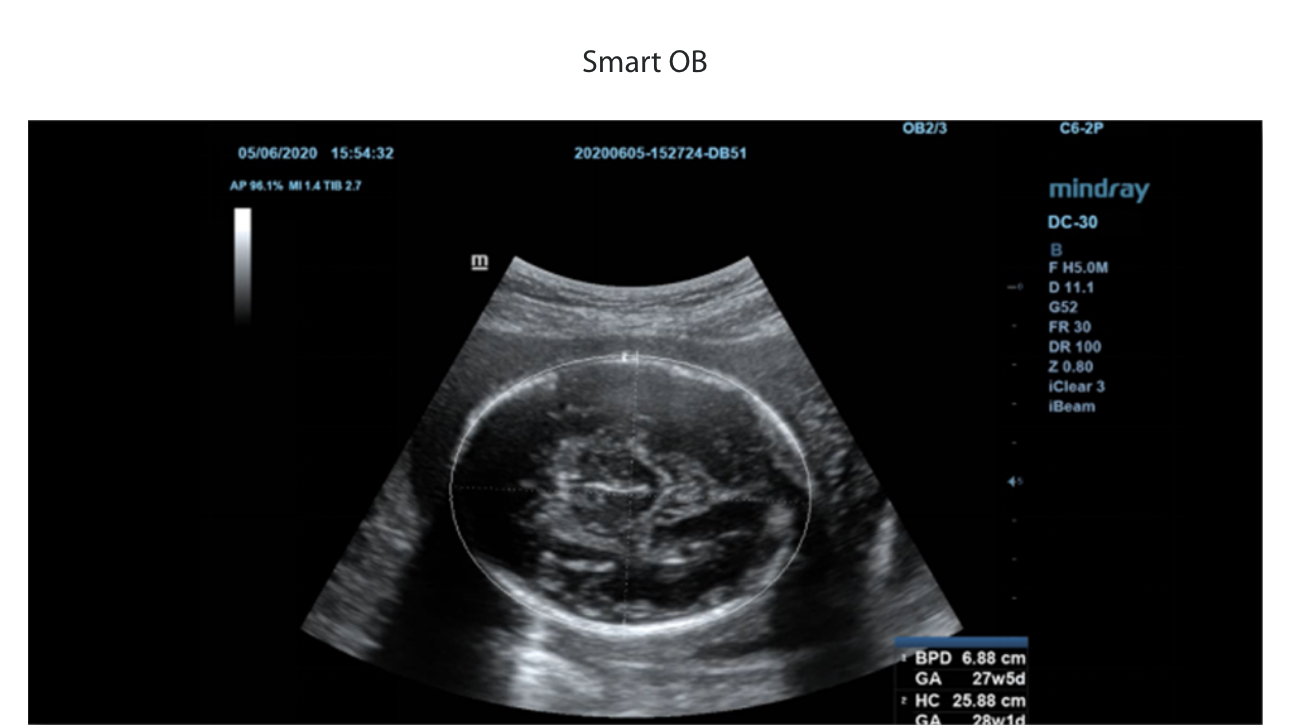

1Ruime keuze aan toepassingsspecifieke onderzoeksvlakken

Vlakpakketten voor verschillende toepassingen: Abdomen, verloskunde/gynaecologie, schildklier, borst, testikel.

Inclusief verschillende (meervoudige) beeldmodi.

170+

Scanvlakken

6+

Onderzoeksmodus

15+

Weefsel orgaan

Ruime keuze aan toepassingsspecifieke onderzoeksvlakken

1

Vlakpakketten voor verschillende toepassingen: Abdomen, verloskunde/gynaecologie, schildklier, borst, testikel.

Incluindo diferentes (m├║ltiplos) modos de imagem.